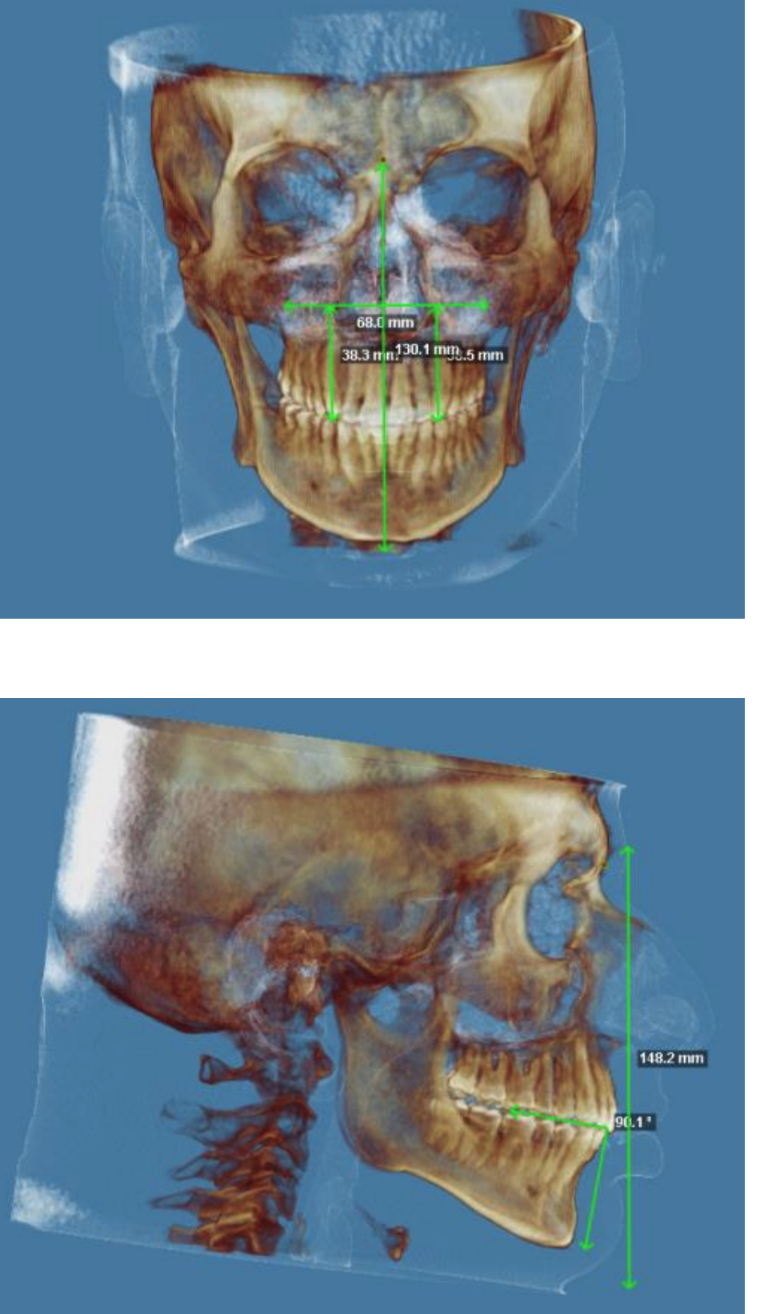

They are planning on doing a segmental 3-piece Lefort 1 which should give me about 5mm of expansion and 8mm of advancement, along with a CCW rotation of a few degrees (my dumbass forgot to ask how many) and a BSSO mandibular advancement of 12mm.

My plans after this surgery are to get a CT scan and have supra/infra-malar implants designed by giant and taken to Pagnoni, and then to have a conservative, closed rhinoplasty to make my nose less overpowering along with a septoplasty which should further improve my breathing.

Feel free to ask any questions, also if any autists out there want to make comments about my scans, current appearance and my surgery plans then please do so.